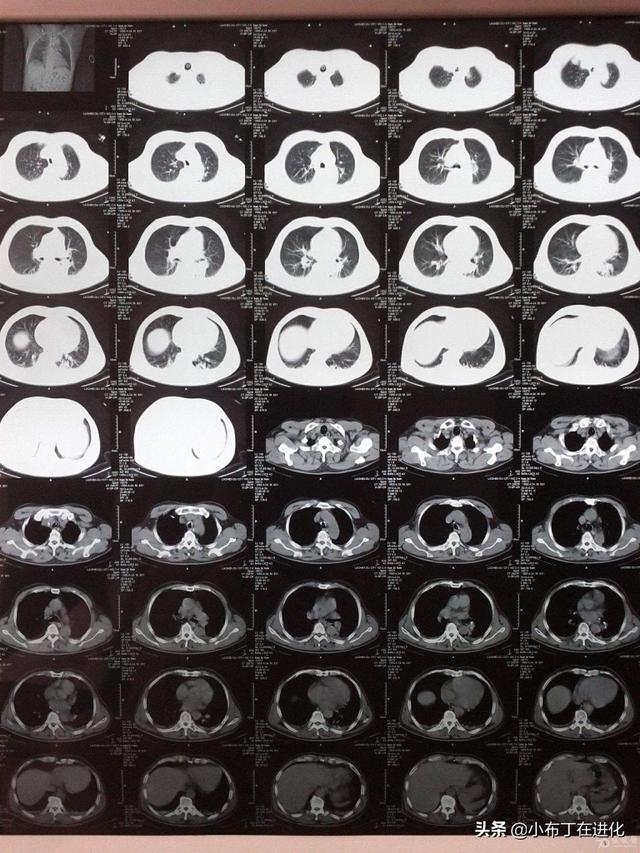

拍胸部CT和颈部CT为什么要24小时才能拿片子

拍胸部CT和颈部CT需要24小时才有结果,综合考虑是因为:1.在大医院,住院病人和门诊病人都很多,有时候一天一个放射科几台CT机不停歇的工作,一天下来最少也有上百个CT片,而且分不同的部位,头颅,脊柱,四肢骨骼,腹部,盆腔,这么多部位,光是操作都要花很多时间了,而且小一点的医院可能就一两台机器,工作效率低,也会影响结果的发布。

2.放射科的医生也会有不同的分工,有自己专攻的领悟,而且当班医生阅片之后还需要主任级别的医生阅后签名审核后才可以发报告的,并且医学是复杂的,人的认识也是有局限性的,有一些疑难杂症单纯靠CT并不一定能明确,只提供一个临床参考,有的时候一个CT片需要反复阅读和反复确认才会发到临床医生和病人手上,毕竟这事关认命的大事,如果草率行事,最终完成误诊和漏诊,受伤害的还是病人和家属,所以我觉得做一个CT,而且是颈部和胸部,这么多部位,24小时出结果并不算太久,如果刚做完就出结果那才觉得奇怪吧。